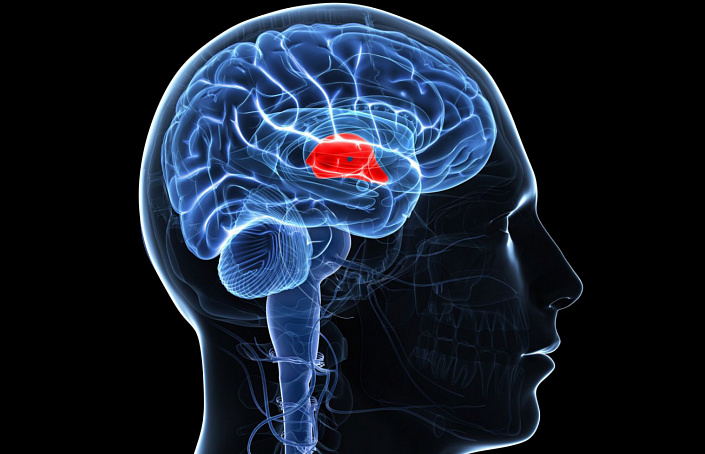

Гипоталамо-гипофизарная система

Гипоталамус и гипофиз в анатомии обычно рассматривают совместно, поскольку обе эти железы выполняют совместную деятельность, регулируя жизненно важные процессы. Несмотря на крайне маленький размер гипофиза, который обычно весит не более 1 грамма, он является важнейшим координирующим центром для всего организма человека. Именно здесь вырабатываются гормоны, от концентрации которых зависит деятельность практически всех остальных желёз.

Анатомически гипофиз состоит из трёх микроскопических долей: аденогипофиза, расположенного спереди, нейрогипофиза, локализованного сзади, и срединной доли, которая, в отличие от двух других, практически не развита. Наиболее значимую роль играет аденогипофиз, синтезирующий 6 ключевых доминирующих гормонов:

- тиреотропин — влияет на деятельность щитовидки,

- адренокортикотропный гормон — отвечает за функциональность надпочечников,

- 4 гонадотропных гормона — регулируют фертильность и половую функцию.

Кроме того, передняя доля гипофиза вырабатывает соматотропин — гормон роста, от концентрации которого напрямую зависит гармоничное развитие костной системы, хрящевой и мышечной ткани, а значит, и пропорциональность тела. Переизбыток соматотропина, вызванный излишней активностью гипофиза, может приводить к возникновению акромегалии — патологическому росту конечностей и лицевых структур.

Задняя доля гипофиза не вырабатывает гормонов самостоятельно. Её функция заключается в воздействии на эпифиз и его гормональную активность. От того, насколько развита задняя доля, напрямую зависит гидробаланс в клетках и сократительная возможность гладкомышечных тканей.

В свою очередь, гипофиз является незаменимым союзником гипоталамуса, осуществляя связь между мозгом, нервной системой и кровеносными сосудами. Подобная функциональность объясняется активностью нейросекреторных клеток, которые синтезируют специальные химические вещества.